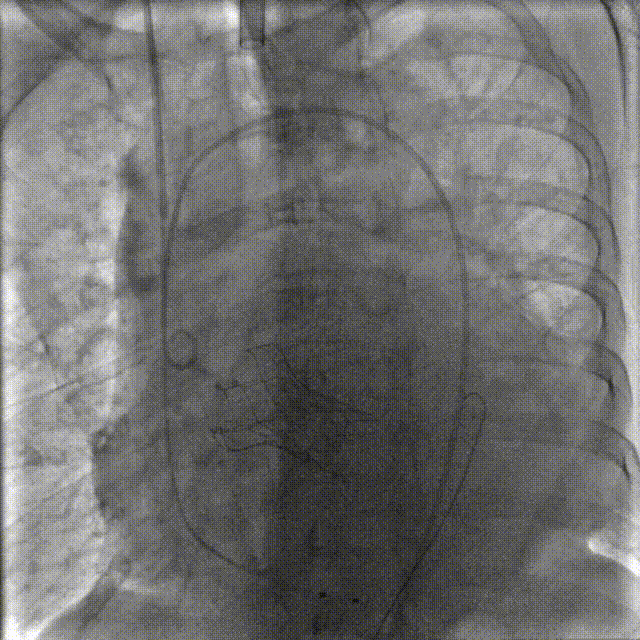

根据术前测量分析,采取右侧股动脉作为主入路,左股为辅入路。置入猪尾进行根部造影,造影可见主动脉根部钙化重,瓣叶活动度低。

1.冠脉造影评估

2.主动脉瓣根部造影

右窦居中,无窦最低

3.微创Alwide 20mm球囊充分预扩张

造影观察左右冠显影情况